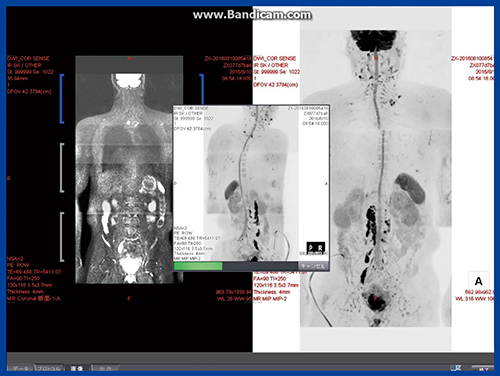

WB-DWIの作成に当たっては,複数枚のDWI画像を集め,3つのstationのWindowを合わせるが,うまく合わないことが多いほか,その後に作成する画像の種類も多く,かつすべての画像の白黒反転処理もあるため,非常に手間のかかる作業となる。熟練の診療放射線技師でも,画像処理を完了するまでに約15分を要していた。

しかし,Ziostation2ではWB-DWIデータ作成の完全自動化が図られ,すべての行程が約1分で終了するようになった。撮像終了後,“マルチステーション結合(W.I.P.)”をクリックして3つのstationの画像を開くと,すぐに図5のような画像が得られるようになり,きわめて有用である。

図5 完全自動WB-DWIデータ作成による画像